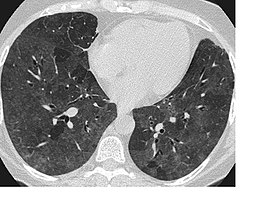

Очаговые изменения

Очаговые изменения в лёгких могут быть разного размера. Очаги мелкого диаметра 1-10 мм выявляются при различных диффузных патологиях лёгочной ткани. Очаги с высокой плотностью и довольно чётки краями в основном наблюдаются в интерстиции лёгкого. Различные очаги низкой плотности, напоминающие матовое стекло, с нечёткими контурами возникают при патологических изменениях в респираторных отделах дыхательных органов.

Нужно учитывать, что плотность и размер очагов имеет слабое диагностическое значение. Для постановки диагноза более важным может быть распределение патологических процессов в лёгочной ткани:

- Перилимфатический очаг – часто наблюдается в бронхах, сосудах, в междольковых перегородках и листках плевры. В таком случае видны неровные контуры анатомических структур, при этом перегородочки и стенки бронхов несколько утолщены, как и стенки сосудов. Подобные патологические изменения часто встречаются при туберкулёзе, силикозе, саркоидозе и карциноматозе. При этих патологиях очаги небольшие и не превышают 2-5 мм. Состоят такие очаги из гранулем или метастатических узелочков, они наблюдаются вдоль лимфатических узелков в ткани лёгких и плевре.

- Полиморфный очаг. Такие очаговые образования в ткани лёгких возникают при туберкулёзе. В этом случае КТ позволяет увидеть участки разной плотности и размеров. В некоторых случаях такая картина наблюдается при онкологических патологиях.

- Центрилобулярные очаги. Наблюдаются в артериях и бронхах или в непосредственной близости от них. Они могут быть довольно плотными, хорошо очерченными и однородными. Изменения лёгочной ткани такого типа наблюдаются при пневмониях, эндобронхиальном туберкулёзе и разных видах бронхита, преимущественно бактериального происхождения. Есть и другой тип центрилобулярных очагов, в этом случае лёгочная ткань имеет мелкие уплотнения и похожа на матовое стекло.

- Периваскулярные очаги – это патологические образования, которые находятся в непосредственной близости от кровеносных сосудов. Такое состояние наблюдается при онкологических патологиях и туберкулёзе. Очаги могут быть как единичные, так и множественные.

- Хаотично расположенные очаги. Такие образования характерны для патологических гематогенных процессов. Это может быть гематогенная инфекция, туберкулёз или метастазы гематогенного типа. Большие множественные очаги, размером около 10 мм, частенько наблюдаются при септических эмболиях, гранулематозе, грибковых инфекциях и метастазах. Все эти заболевания имеют некоторые отличия, по которым их можно дифференцировать.

- Субплевральные очаги – это патологически изменённые участки, расположенные под плеврой. Наблюдение таких участков на снимке всегда говорит о развитии туберкулёза или онкологических заболеваний.

- Плевральные очаги. Такие патологические образования расположены на плевре. Наблюдаются при воспалительных и инфекционных патологиях нижних дыхательных органов.

- Апикальный очаг представляет собой чрезмерное разрастание фиброзной ткани, которая со временем замещает здоровые клеточки.

- Лимфогенный карциноматоз. Это понятие включает два типа патологических изменений в лёгких. С правой стороны наблюдается альвеолярная инфильтрация, с видимыми просветами бронхов. С левой стороны плотность лёгочной ткани несколько повышена. В зоне уплотнения наблюдаются стенки бронхов и сосудиков.

При очаговых заболеваниях участки патологически изменённой ткани могут быть разными по размерам. Они могут быть мелкими, размером не более 2 мм, средними – диаметром до 5 мм и крупными, размер последних превышает 10 мм.

Патологические очаги бывают плотными, средней плотности, а также рыхлыми. Если в лёгких наблюдаются единичные уплотнения, то это может быть как возрастным изменением, которое не представляет опасности для человека, так и опасным заболеванием. Если наблюдаются множественные очаги, то здесь речь идёт о воспалении лёгких, туберкулёзе или редких формах онкологических заболеваний.